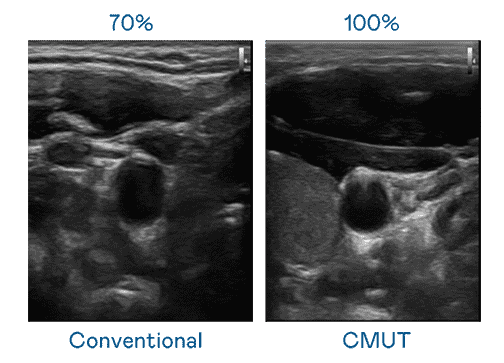

CMUT 技术是一种用电容式微机电元件来产生超音波讯号的技术。。。。与传统 PZT 压电式技术相比,,,,CMUT 频宽增加 30%,,更宽频的超音波讯号让影像解析度大幅提升,,是实现高影像品质医疗超音波扫描、、、、促进精准医疗发展的关键技术。。

大频宽带来超清晰影像

超音波影像的解析度高低,,首先取决于探头能发出的讯号频宽。。。。NG大舞台 CMUT 可提供高清晰的超音波讯号,,提供高频宽、、、高灵敏度、、、、影像纹理细节更高的超音波影像,,协助医护人员缩短影像判读时间及利用精准的医疗影像进行诊断。。